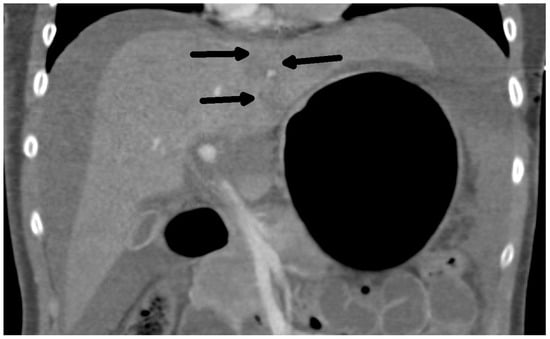

The diagnosis of liver injury was made by clinical and paraclinical examination and confirmed by imaging techniques. (computed tomography (CT) or ultrasound) (Table 2) (Figure 1 and Figure 2).

Figure 2.

CT scan: Rupture of the liver along falciform ligament (arrows) and hemoperitoneum frontal view.